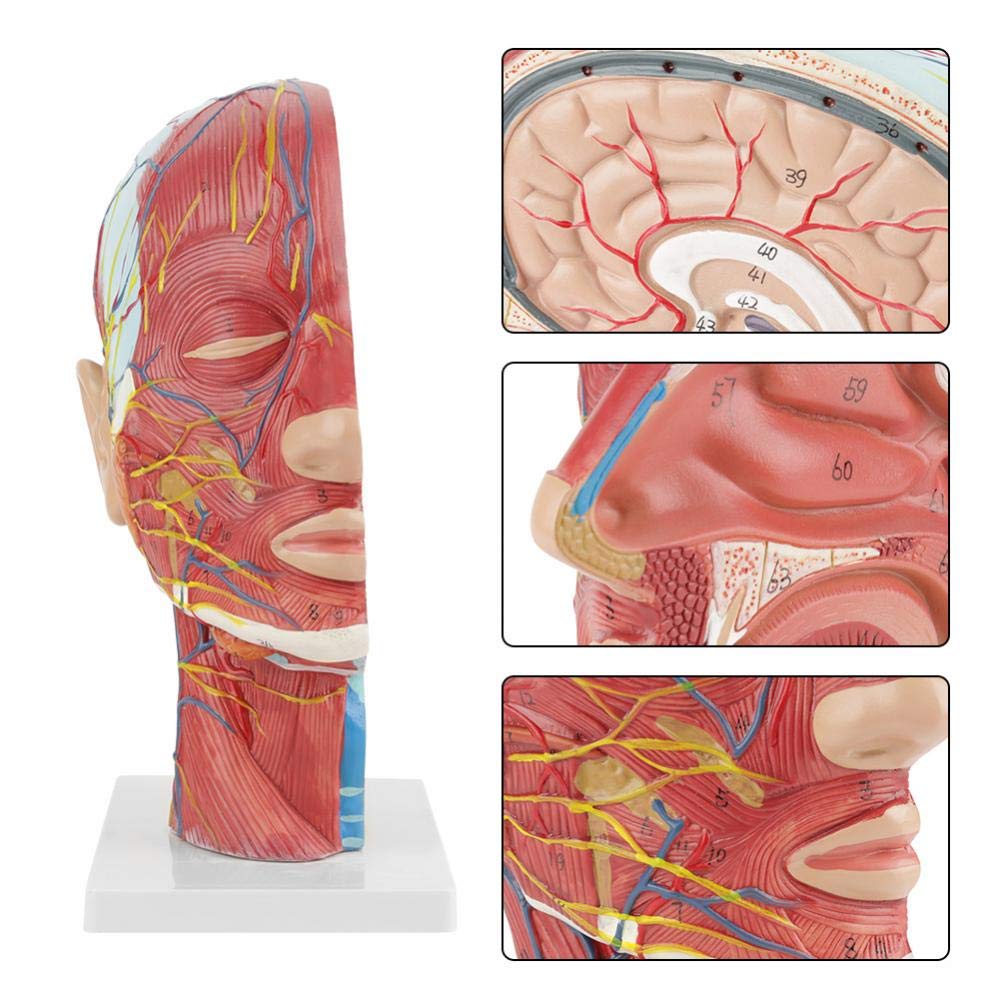

מענטשלעך האַלב קאָפּ & האַלדז אַנאַטאָמי מאָדעל אויבנאויפיקער נעוראָוואַסקולאַר מאָדעל

מענטשלעך האַלב קאָפּ & האַלדז אַנאַטאָמי מאָדעל אויבנאויפיקער נעוראָוואַסקולאַר מאָדעל

| פּראָדוקט נאָמען | מענטשלעך שאַרבן מיט מוסקל נעוראָוואַסקולאַר מאָדעל |

| ויסמעסטונג | 21 * 12 * 27 קם |

| פֿעיִקייטן | דער מאָדעל ווייזט די היגע מאָרפאַלאַדזשי פון די ינער און ויסווייניקסט זייטן פון די מידיאַן סאַגיטטאַל אָפּטיילונג פון די קאָפּ און האַלדז, און די סטראַקטשערז פון בלוט כלים און נערוועס און עס זענען 84 פּאַרץ ינדאַקייטינג וואונדער אין גאַנץ. |

【1: 1 לייווז】 מידיאַן אָפּטיילונג פון 1: 1 נאַטירלעך גרויס קאָפּ & האַלדז אויבנאויפיקער נעוראַל וואַסקיאַלער מוסקל מאָדעל (רעכט זייַט). פייַן ווערקמאַנשיפּ. פאָרשלאָגן אַ פול קייט פון אַנאַטאַמיקאַל פֿעיִקייטן.

【הויך קוואַליטעט】 מאַרך אַנאַטאָמי מאָדעל, געמאכט פון ניט-טאַקסיק ינווייראַנמענאַלי פרייַנדלעך פּווק מאַטעריאַל, גרינג צו ריין. אַנאַטאָמי מאָדעלס זענען האַנט-פּיינטיד און פארזאמלט מיט די מאַקסימאַל ופמערקזאַמקייט צו דעטאַל.

【Superficial Neurovascular Muscle Model】Highly detailed, numbers marked, detachable ear, deepen the understanding of the superficial muscles, vessels, nerves and the internal structures of the head & neck. רויט-אַרטעריע, בלוי-אָדער, געל-נערוו.

【פֿעיִקייטן】 עס געוויזן די אויבנאויפיקער מאַסאַלז פון די יקספּאָוזד פּנים; די אויבנאויפיקער בלוט כלים & נערוועס פון די פּנים & סקאַלפּ; די ינער סטראַקטשערז פון פּאַראָטיד דריז & אויבערשטער רעספּעראַטאָרי שעטעך; די סאַגיטטאַל קרייַז-אָפּטיילונג סטרוקטור פון די סערוואַקאַל רוקנביין.

【אַפּלאַקיישאַן】 דעם מאָדעל איז דער ערשטער ברירה פֿאַר דער דאָקטער ס אָפיס, שולע, האָסיפּאַטאַל און קליפּס. טאַקע אַ גרויס לערנען הילף פֿאַר אַנאַטאַמי & פיזיאַלאַדזשי קאָרסאַז, דעמאַנסטריישאַן, קאָמוניקאַציע געצייַג פֿאַר דאקטוירים און פּאַטיענץ.

דער מאָדעל ווייַזן דעטאַילס פון די רעכט קאָפּ האַלדז און מיטן סאַגיטטאַל אָפּטיילונג פון דער מענטש. אַרייַנגערעכנט די אויבנאויפיקער

מאַסאַלז פון די יקספּאָוזד פּנים; די אויבנאויפיקער בלוט כלים און נערוועס פון די פּנים און סקאַלפּ; די ינער סטראַקטשערז

פון פּאַראָטיל דריז און אויבערשטער רעספּעראַטאָרי שעטעך; די סאַגיטטאַל קרייַז-אָפּטיילונג סטרוקטור פון די סערוואַקאַל רוקנביין.

דער מאָדעל געוויזן די היגע מאָרפאַלאַדזשי פון די מעדיאַל און לאַטעראַל סאַגיטטאַל סעקשאַנז פון די קאָפּ און האַלדז און די וואַסקיאַלער און נערוו סטראַקטשערז, מיט אַ גאַנץ פון 100 פּלאַץ ינדאַקייטערז.

דער מאָדעל איז נאַטירלעך גרויס קאָפּ און האַלדז אויבנאויפיקער נעוראָוואַסקולאַר מוסקל מאָדעל, 1 קאָמפּאָנענט, ווייַזונג די דעטאַילס פון די מענטשלעך רעכט קאָפּ און מעדיאַן סאַגיטטאַלע אָפּטיילונג, אַרייַנגערעכנט די יקספּאָוזד בעשאָלעם און די מעדיאַל סטרוקטור פון די פּאַראָטיד דריז און אויבערשטער רעספּעראַטאָרי שעטעך, און די סאַגיטטאַל אָפּטיילונג סטרוקטור פון די סערוואַקאַל רוקנביין